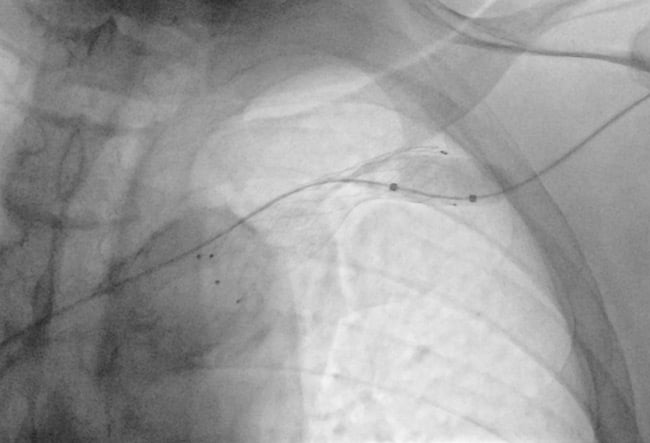

The fistulography, performed via the cephalic vein percutaneous access, confirmed the stent occlusion (3) and suggested a possible misalignment with the central venous route.

The initial retrograde approach through cephalic vein puncture failed to cross the occlusion.

We then attempted a venous transfemoral approach, positioning a 7F, 65-cm introducer sheath with its tip in the superior vena cava.

Phlebography confirmed complete occlusion (4). Multiple catheters and guidewires were employed, but without success.